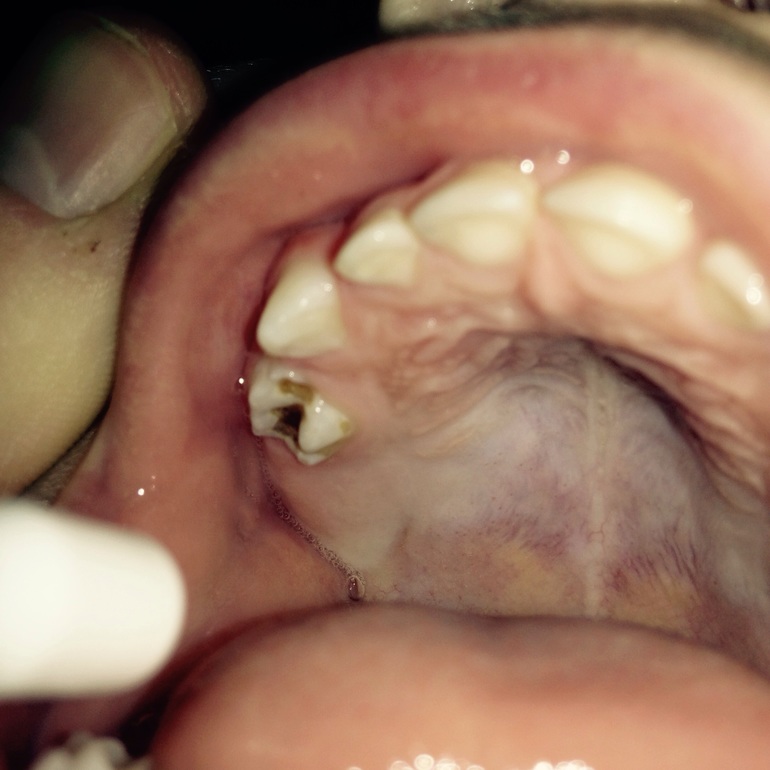

Черное пятно на жевательном зубе.

здравствуйте, сыну 2 года заметили большое черное пятно на верхнем жевательном зубе. Это кариес? Что делать с ним? Спасибо!

Здравствуйте.Это даже больше похоже на пульпит- воспаление нерва. Но, если и нерв не задет, такой зуб нужно пломбировать с анестезией. Без анестезии будет больно и неэффективно(